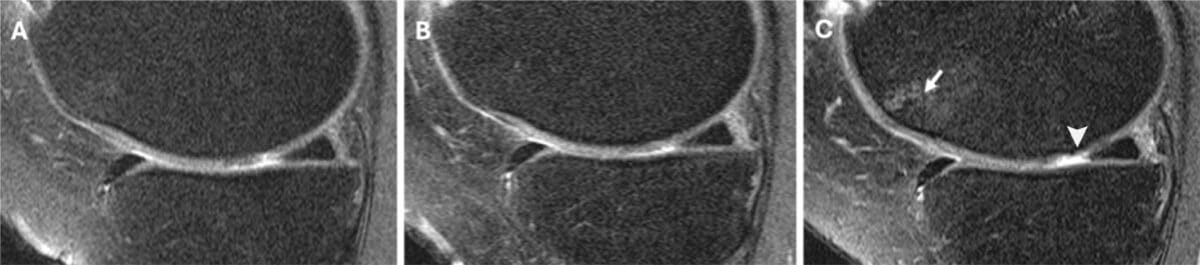

What set this study apart was its use of detailed MRI scans to assess joint health. Researchers evaluated images from two years before the injection, at the time of injection, and again two years afterward using the Whole-Organ MRI Score (WORMS). This scoring system provides a comprehensive assessment of cartilage, bone marrow, meniscus, ligaments, and joint effusion.

MRI images helped visualize the contrast. In a 58-year-old woman who received a steroid injection, follow-up scans showed new full-thickness cartilage lesions and bone marrow damage. In a 57-year-old man who received hyaluronic acid, the same cartilage remained intact and unchanged over four years.

Researchers conducted a secondary analysis of data from the Osteoarthritis Initiative, following 210 participants (mean age 64 years, 60% female) over multiple years. They used detailed 3-T MRI scans taken at three time points: two years before injection (T-2), at the time of injection (T0), and two years after injection (T+2). The study compared three groups—those who received corticosteroid injections (44 people), hyaluronic acid injections (26 people), and propensity-score matched controls who received no injections (140 people). Joint health was measured using the comprehensive Whole-Organ MRI Score (WORMS) system rather than simple X-rays. Only participants with a single injection during the study period were included.

Corticosteroid injections were associated with greater WORMS progression compared to both controls (mean difference, 0.39; 95% CI: 0.05, 0.75; P = .02) and hyaluronic acid injections (0.42; 95% CI: 0.01, 0.84; P = .04) over the two-year follow-up period. Hyaluronic acid injections showed decreased progression compared to the pre-injection period (mean difference, −0.42; 95% CI: −1.34, −0.28; P = .003). Both injection types delivered pain relief, with corticosteroid injections reducing WOMAC pain scores by 5.20 points (P = .001) and hyaluronic acid by 2.15 points (P = .04). The differences were particularly notable in cartilage deterioration.